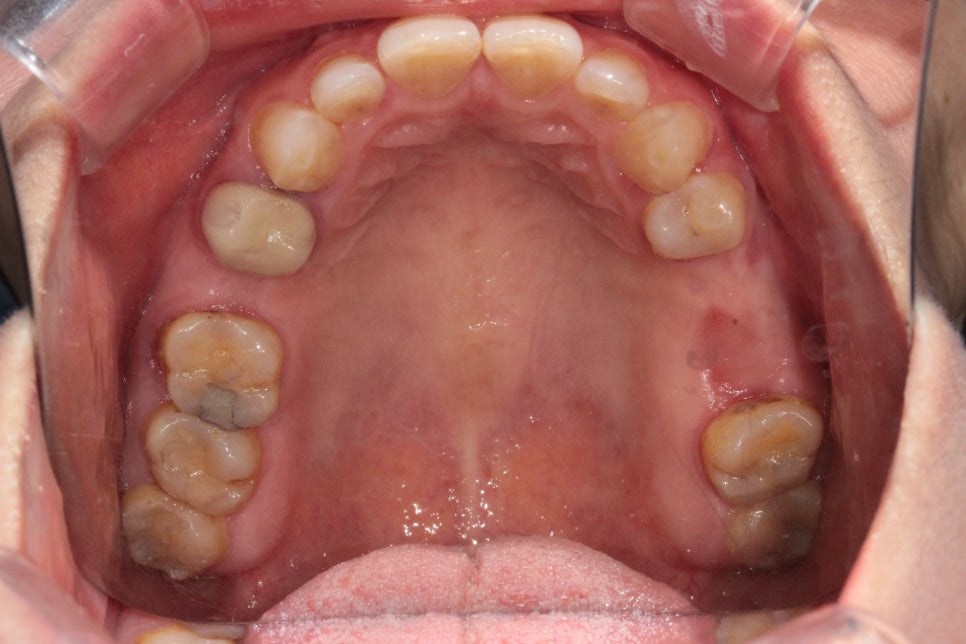

위쪽 치아 교합면 사진

반면 바로 옆 두번째 작은 어금니 부위는

11.4mm의 충분한 골 높이가

확보가 되어있었고요.

아래쪽 치아 교합면 사진

치료시작 전 전체 치아 사진